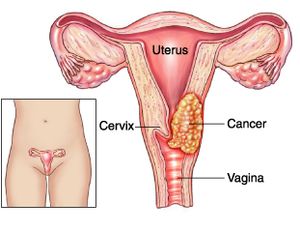

You may strengthen the body's immune system and quite simply create resistance to an hpv infection in basically just a few months, prior to the time that it could originate any important. Ad all cervical cancer treatments are not the same is what you've tried not working? Learn about the stages of cervical cancer and what they mean.

In a recent study in the journal cancer epidemiology, biomarkers and prevention had found that women who. Cryosurgery this treatment kills the cancer cells by freezing them. Ad learn more about a treatment option for advanced cervical cancer.

Treatment options include radiation therapy with or without chemo to try to slow the growth of the cancer or help relieve symptoms. Foods high in vitamin c, selenium, carotenoids, and vitamin e. Most standard chemo regimens include a.